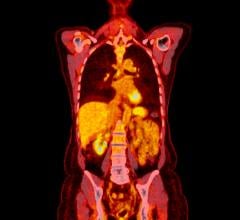

rhPSMA compounds are referred to as radiohybrid (“rh”), as each molecule possesses three distinct domains. The first consists of a Prostate-Specific Membrane Antigen-targeted receptor ligand which attaches to and is internalized by prostate cancer cells. It is attached to two labelling moieties which may be radiolabeled with diagnostic isotopes such as 18F or 68Ga for PET imaging, or with therapeutic isotopes such as 177Lu or 225Ac for radioligand therapy – enabling the potential for a true theranostic technology. They may play an important role in patient management in the future, and offer the potential for precision medicine for men with prostate cancer. Radiohybrid technology and rhPSMA originated from the Technical University of Munich, Germany. Blue Earth Diagnostics acquired exclusive, worldwide rights to rhPSMA diagnostic imaging technology from Scintomics GmbH in 2018, and therapeutic rights in 2020, and has sublicensed the therapeutic application to its sister company Blue Earth Therapeutics. Blue Earth Therapeutics and Blue Earth Diagnostics work closely on the development of 177Lu-rhPSMA-10.1. Currently, Blue Earth Therapeutics’ rhPSMA compounds have not received regulatory approval.